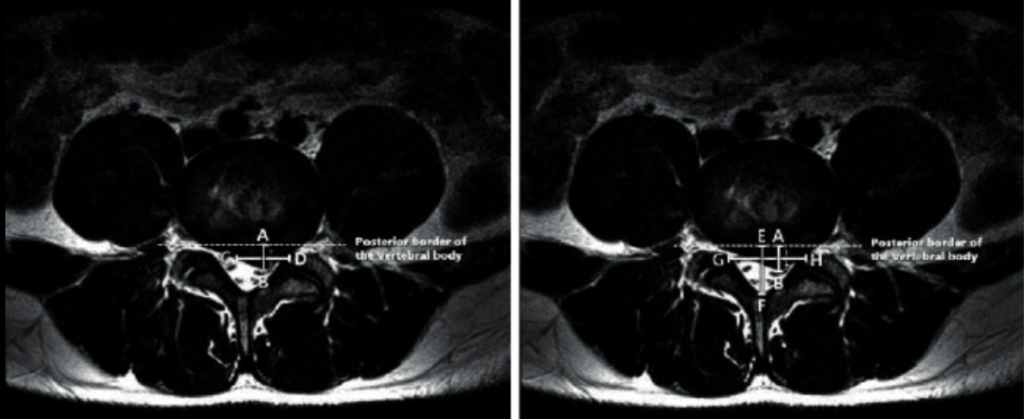

Figure 2

Méthodes de calcul de l’indice de hernie (HI) dans le plan axial de l’imagerie par résonance magnétique (IRM). AB : la longueur maximale du disque antéro-postérieur, qui est le diamètre du matériau discal hernié étendu au maximum à partir de la bordure postérieure du corps vertéral. CD : la largeur du matériau discale hernique au niveau de la distance moyenne AB du matériau herniaire du plan coronal de l’IRM. EF : la longueur maximale du canal antéropostérieur. GH : distance moyenne AB. HI a été calculé à l’aide de la formule suivante :